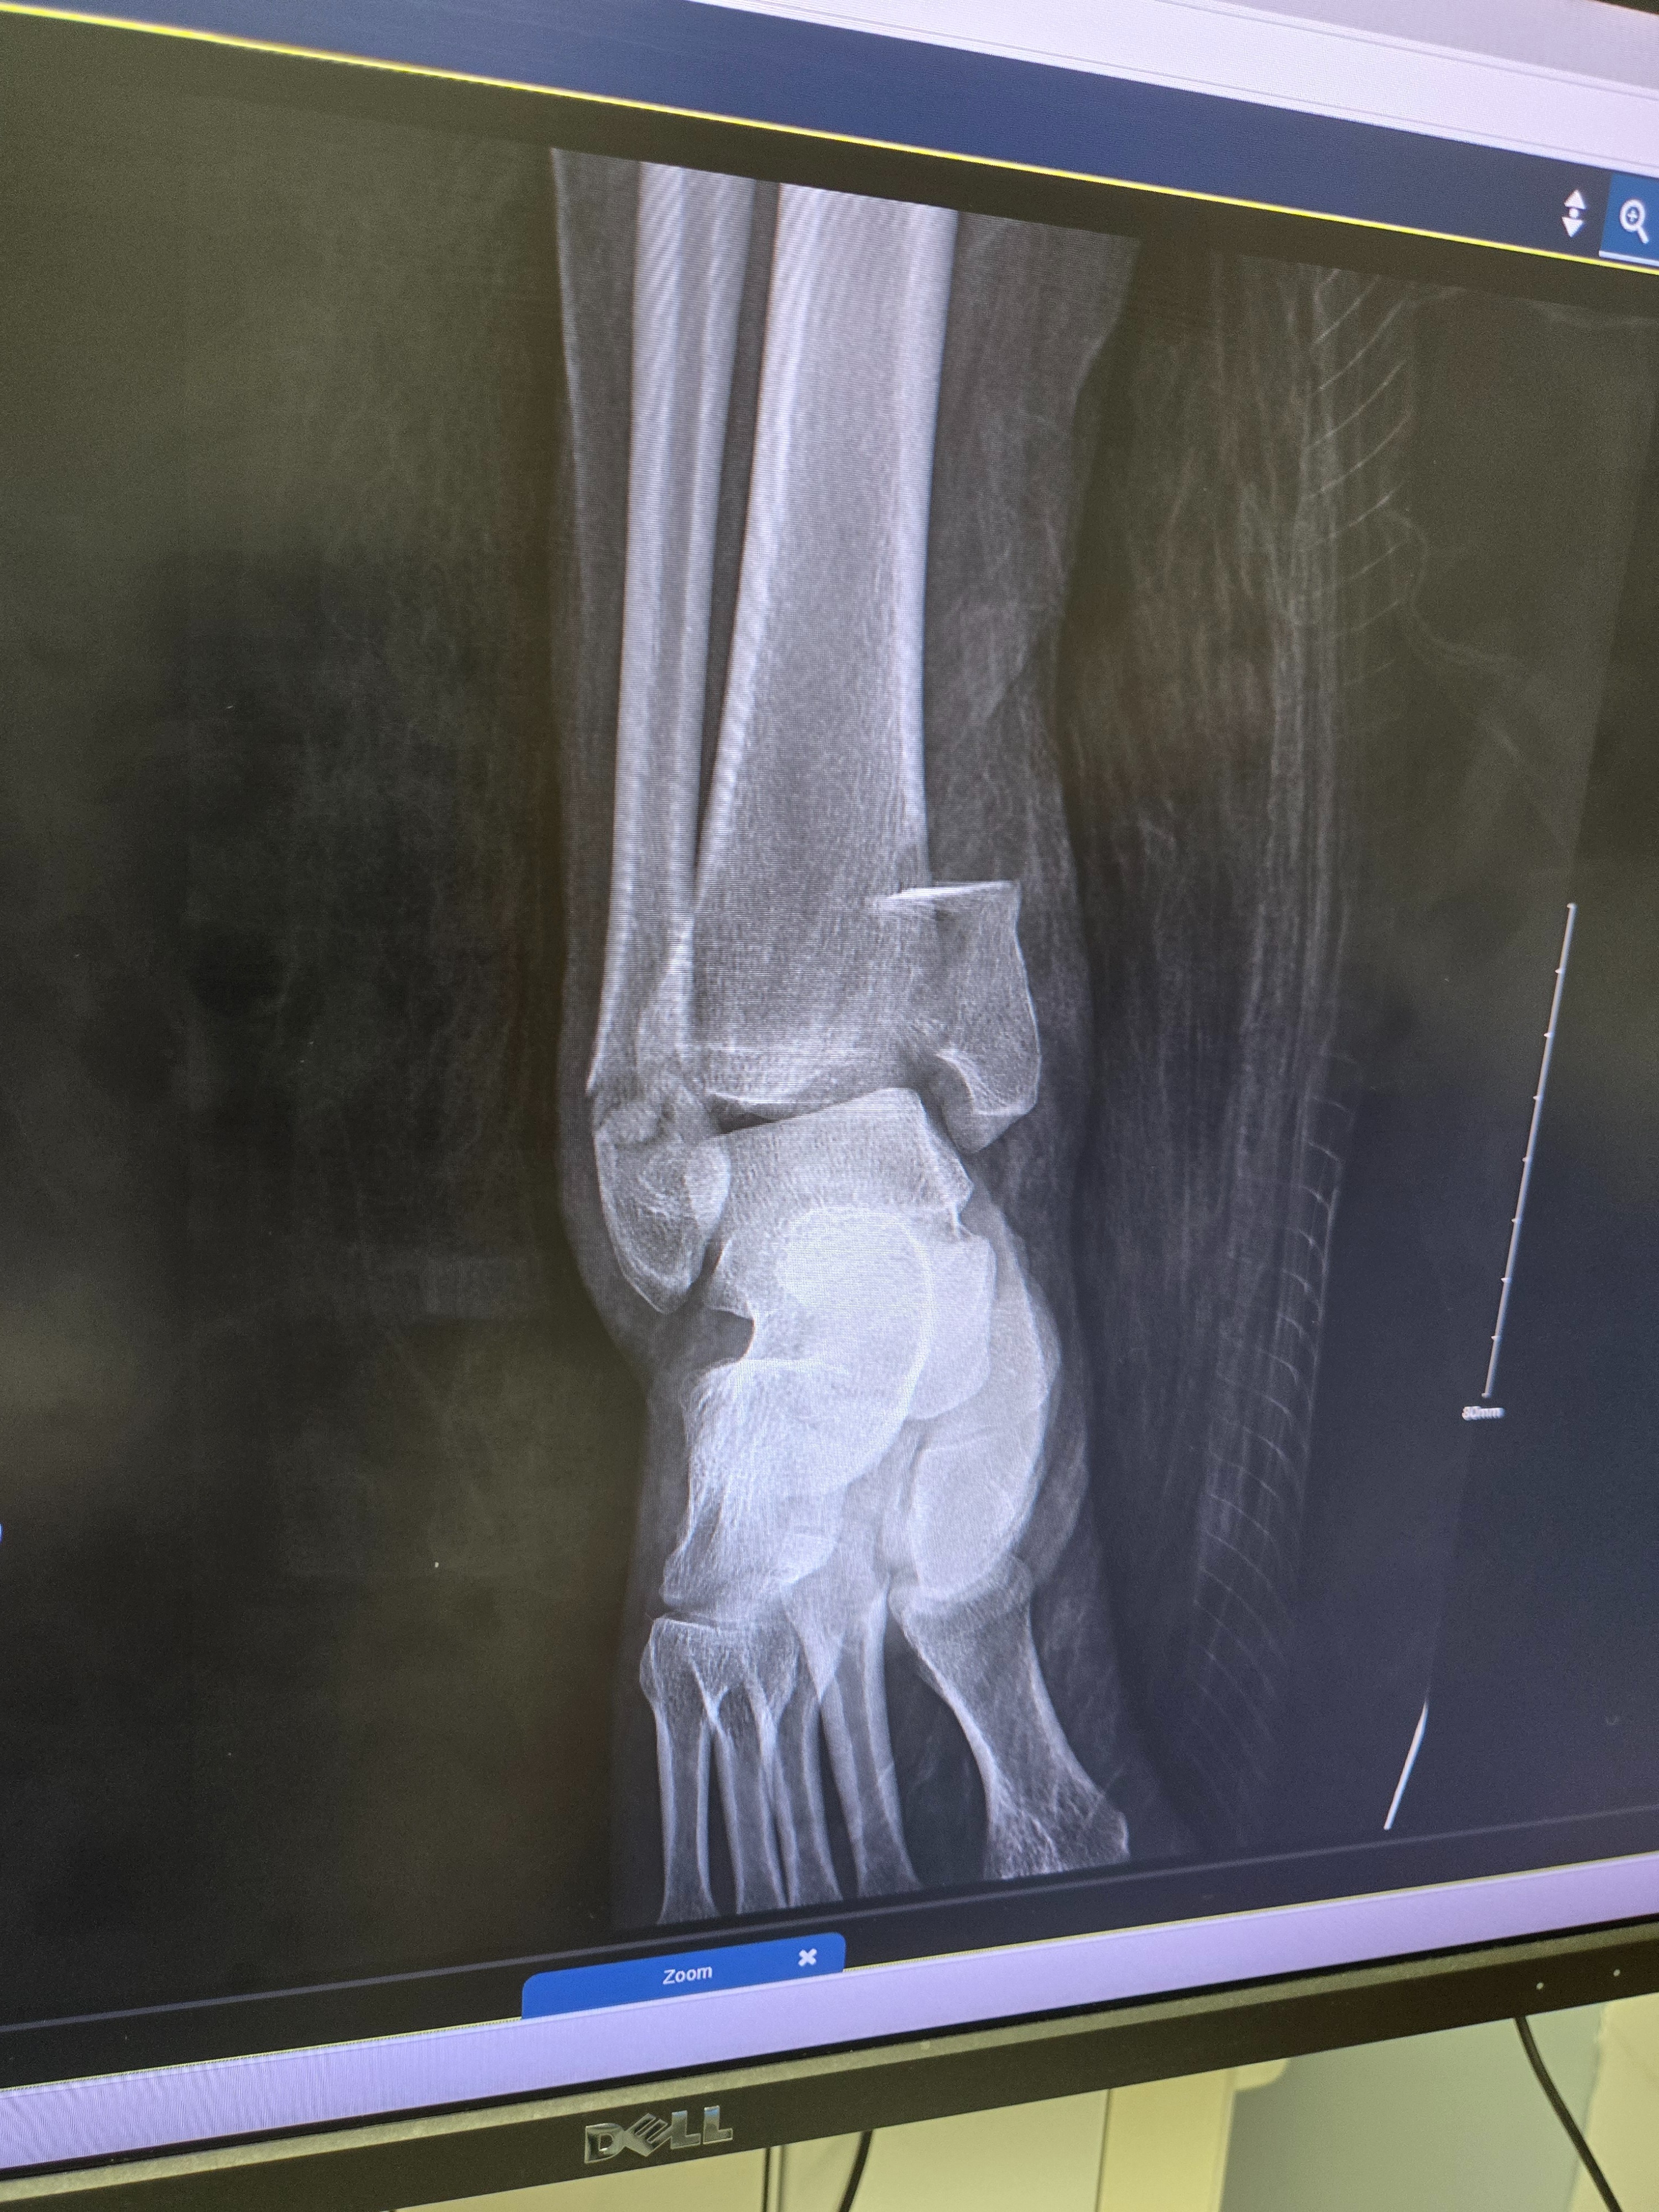

I SURVIVED!!!! My name is Rachel Blackowski, 31 years young.. I was in a severe car accident on Oct 4th . Spent a week in the hospital and have been in rehab. Broken wrist on the left hand (& I'm a lefty) Broken right leg, ankle and knee, non weight bearing injuries for both have me in the wheelchair for an estimated 12 weeks. Have gone through 3 surgeries so far with more to come. Looking at a 6-8 months minimum recovery. Unable to work to provide living wages & owe medical bills. Usually I would be too stubborn & prideful to ask for help ... but this has humbled me to realize I need to lean onto others in my time of need and it is okay. Thank you for any help offered.